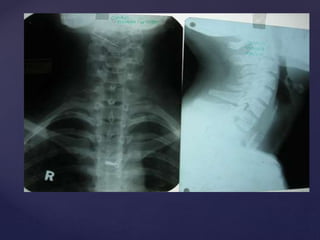

Fig 1

Fig 2

{ {

 Plain X Ray neck ,

chest and abdomen

AP view.

 Showing a round

radio opaque foreign

body in the

esophagus.

 Probably a coin.

 Plain X Ray neck

Lateral view.

 Showing edge on

view in lateral view

suggesting of FB in

oesophagus (in

contrast to FB

trachea)

Foreign Body Oesophagus (Coin)

Foreign Body Trachea